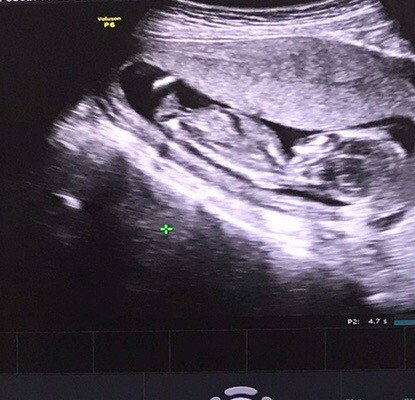

เมื่อวานไปหาหมอซาวด์ท้องเห็นไม่ชัดคุณหมอเลยใช่วิธีสอด เห็นชัด ได้ยินเสียงหัวใจ 6สัปดาห์ ได้ยาบำรุงเลือดมาทานหลังจากกลับเราไปเดินห้างต่อปรากฏว่าเลือดออกเยอะมากต้องใส่ผ้าอนามัยเปลี่ยนไป2แผ่น แผ่นที่3เช้ามา ก็ยังมีเลือดแต่ไม่เยอะเท่าเมื่อวาน ท้องแรกจิตใจกังวลกลัวไปหมด ตอนนี้ใส่แผ่นที่4 ถ้าหยุดไหลก็พอให้สบายใจถ้าไม่หยุดไหลต้องไปโรงพยาบาล แม่ๆท่านไหนเป้นไหมคะ น้องจะเป้นอะไรไหม หรือเพราะเราเดินเยอะ🥺🥺 #ขอบคณสำหรับคำตอบล่วงหน้านะคะ #ท้องแรก #คอมเม้นท์มาหน่อยคะ